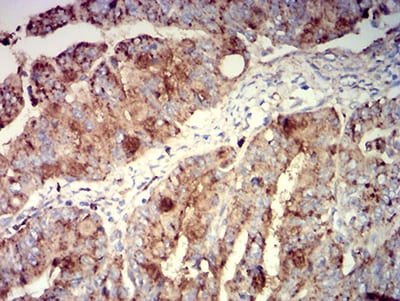

分类: 科研抗体货号: 31424别名: MLA1; ME491; LAMP-3; OMA81H; TSPAN30应用: IHC,FCM反应种属: Human

分类: 科研抗体货号: 31423别名: MLA1; ME491; LAMP-3; OMA81H; TSPAN30应用: IHC,FCM反应种属: Human